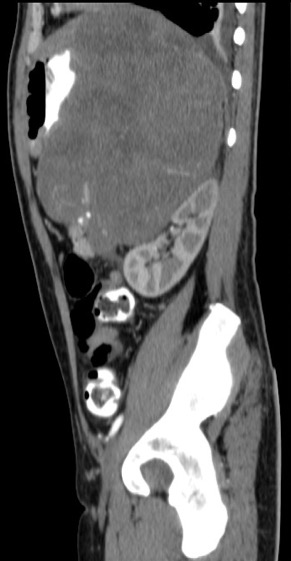

Gastric abnormalities show nonspecific gastrointestinal symptoms and similarly radiological findings. Intra and extra luminal gastric wall thickening are the most common finding in benign and malignant pathologic process. This aim of this case report was to describe several characteristics such as the location and size of the lesion, involvement of the gastric wall and surrounding structures, calcifications, and contrast enhancement pattern which can assist in radiological diagnosis. Several cases at our institution have similar gastrointestinal complaints, however, there were different lesions characteristic found in contrast enhanced abdominal CT scan. The first case 72-years-old man experienced hematemesis with radiologic finding diffuse gastric mucosal thickening as well as homogenous contrast enhancement but without calcification. The second case 37-years-old man complaint dizziness and melena with radiologic finding large tumor more than 10 cm in size, amorph calcification and heterogenous contrast enhancement. The last 60-years-old man case experienced melena and hematemesis, from abdominal CT scan showed irregular gastric mucosal thickening with heterogenous contrast enhancement and fat stranding around the lesion, without calcification. Methods used in these cases were contrast-enhanced abdominal CT scan, esophagogastroduodenoscopy (EGD), and biopsy in order to determine the diagnosis. Contrast-enhanced abdominal CT scan plays a vital role in describing the lesion characteristics which affects the determination of treatment options and future prognosis.